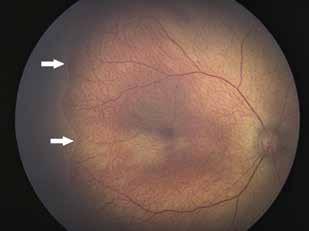

rounding MNV shows greater flow deficits compared to other areas of the macula. This perilesional dark halo in treatment-naïve eyes suggests that RPE hypoxia caused by choriocapillaris disruptions may drive the release of VEGF and the development of MNV.9,17,20,22 As initially hypothesized, patients with MNV may exhibit more localized choriocapillaris impairment, with greater reserve to guide the angiogenesis process, while eyes with atrophic AMD may show more diffuse choriocapillaris lesions, setting the stage for progressive tissue loss as opposed to neovascularization.23,24 Moreover, it has been observed that the choriocapillaris in the peripheral macula differs depending on the MNV subtype, with severe impairment in Type 3 MNV eyes compared to Type 1/2 MNV eyes.25 The widespread choriocapillaris impairment in Type 3 MNV eyes may also explain why these eyes are more prone to developing atrophy compared to Type 1 MNV eyes. However, MNV can also be secondary to other conditions such as high myopia. 26 In pathologic myopia, the progressive posterior segment elongation and deformation may lead to mechanical stress on the retina, causing an imbalance between pro-angiogenic and anti-angiogenic factors, resulting in myopic MNV.27–30 Supporting this, the presence of lacquer cracks has been shown to be a predisposing factor for the development of myopic MNV. 28–30 To

diagnose myopic MNV, a multimodal imaging approach based on fundus biomicroscopy, FA, ICGA, OCT and OCTA is recommended. Most myopic MNVs present as Type 2 lesions, and the number of anti-VEGF injections required for myopic MNV is generally lower than those required for AMD.31,32 (Figure 4)